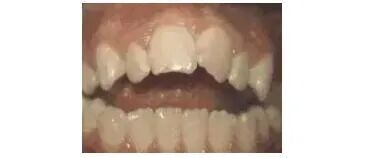

第九种: 深覆盖,咬牙时,上牙差不多完全把下牙挡住了,经过矫正后的牙齿是这样的。